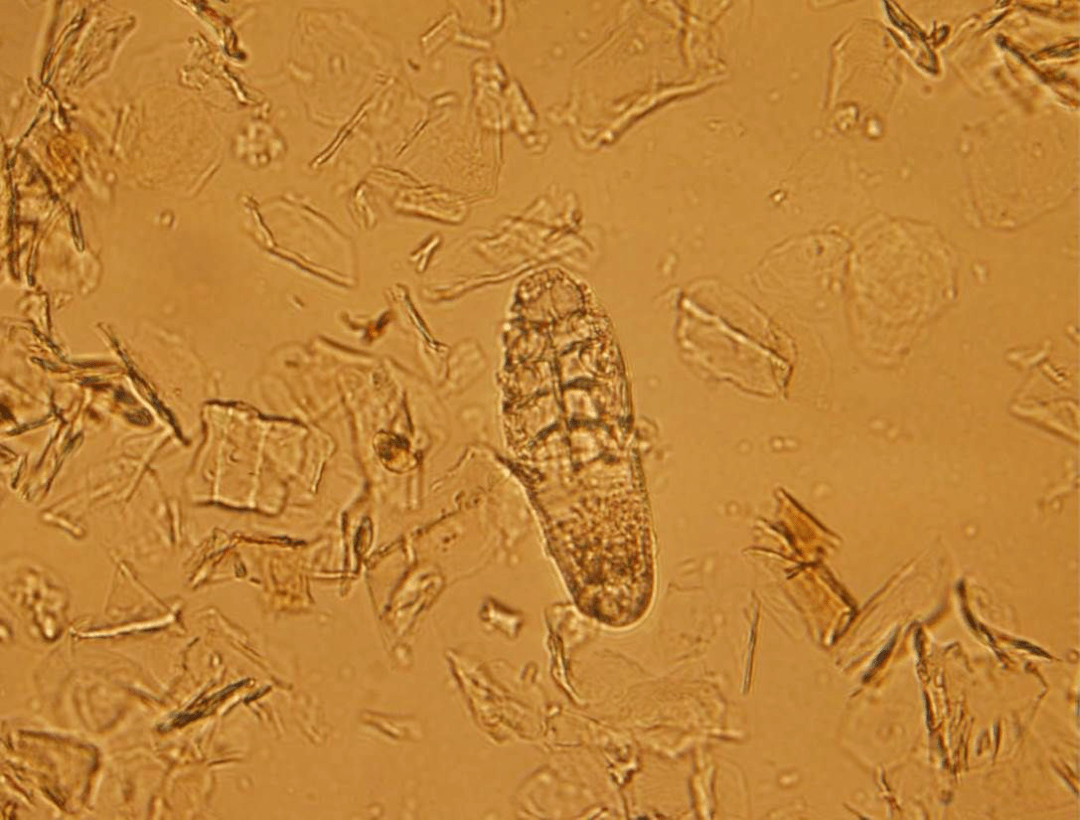

【病例分享】蠕形螨

图片尺寸1280x960